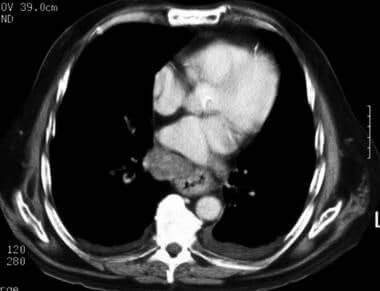

КТ може допомогти виявити захворювання стравоходу кількома способами. По-перше, КТ може виявити аномалії в стравоході, такі як пухлини, стриктури (звуження) або запалення. Зображення, отримані за допомогою КТ, можуть також показати, чи поширилася пухлина на сусідні лімфатичні вузли або органи, що може допомогти лікарям визначити стадію раку. Крім того, КТ може виявити інші захворювання, які можуть бути причиною симптомів пацієнта, такі як грижа стравохідного отвору діафрагми або виразка.